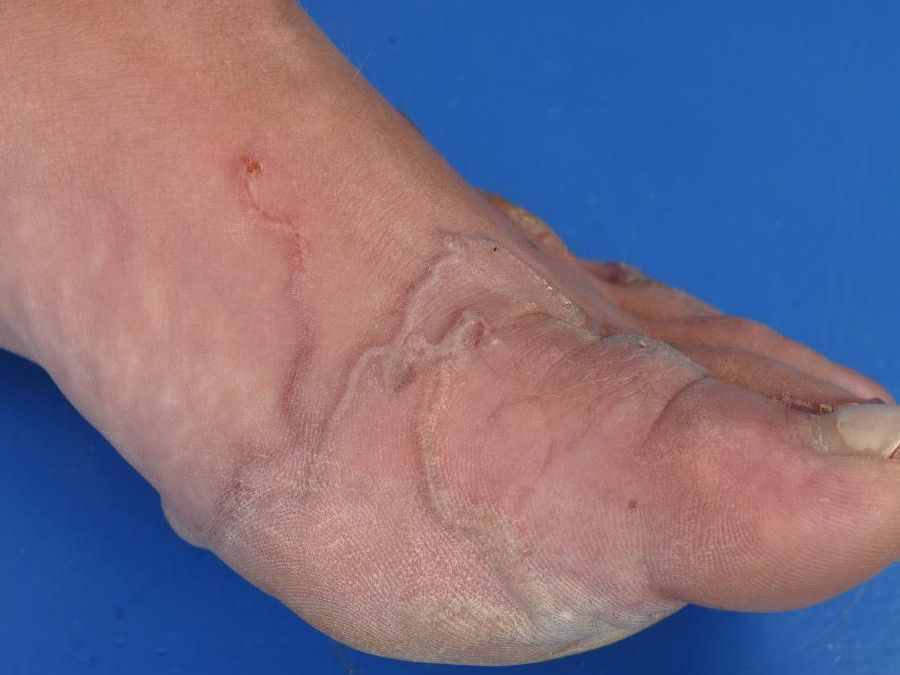

Creeping eruption (larva cutanea migrans) door Ancylostoma braziliensis Creeping eruption (larva cutanea migrans) door Ancylostoma braziliensis Creeping eruption (larva cutanea migrans) door Ancylostoma braziliensis